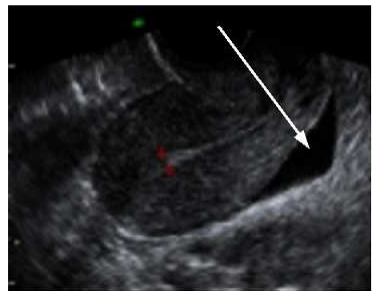

10.一中年女性因發燒及腹痛至醫院掛急診並 接受 X 光檢查 ,下列中何者為箭號所示最可能的診斷:(A)肺膿瘍 (B)肝腫瘤 (C)肝膿瘍 (D)氣胸